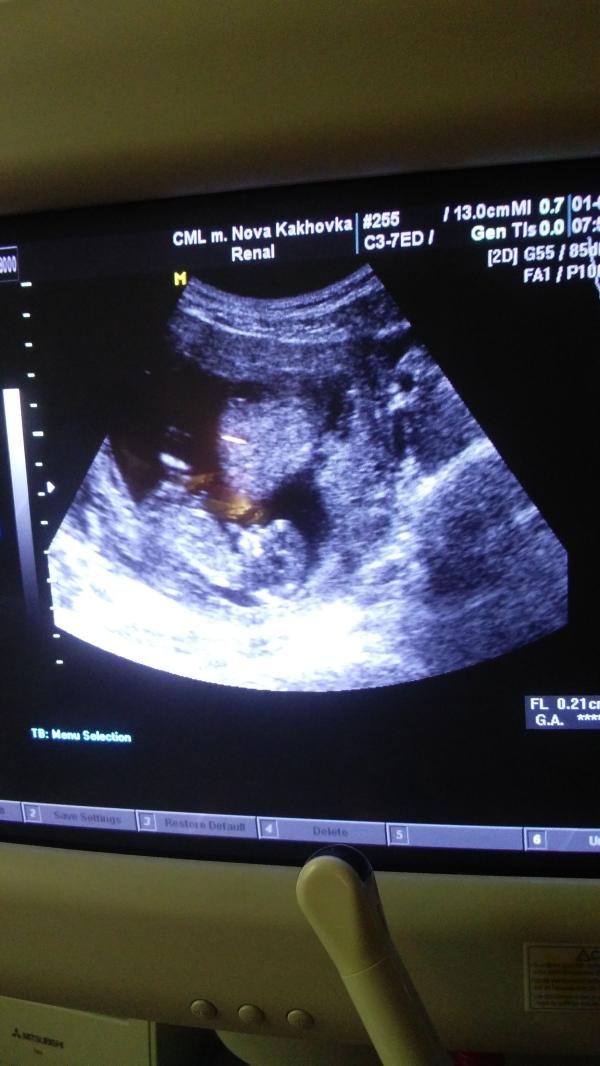

Показала мужу фото с УЗИ - говорит мальчик, по форме головы, нашла фото с родившимися малышами, где уже указан пол - все сказал верно! А вы как думаете? :) Безумно любопытно, кто же там))))

Да, на фото 12 с половиной недель))